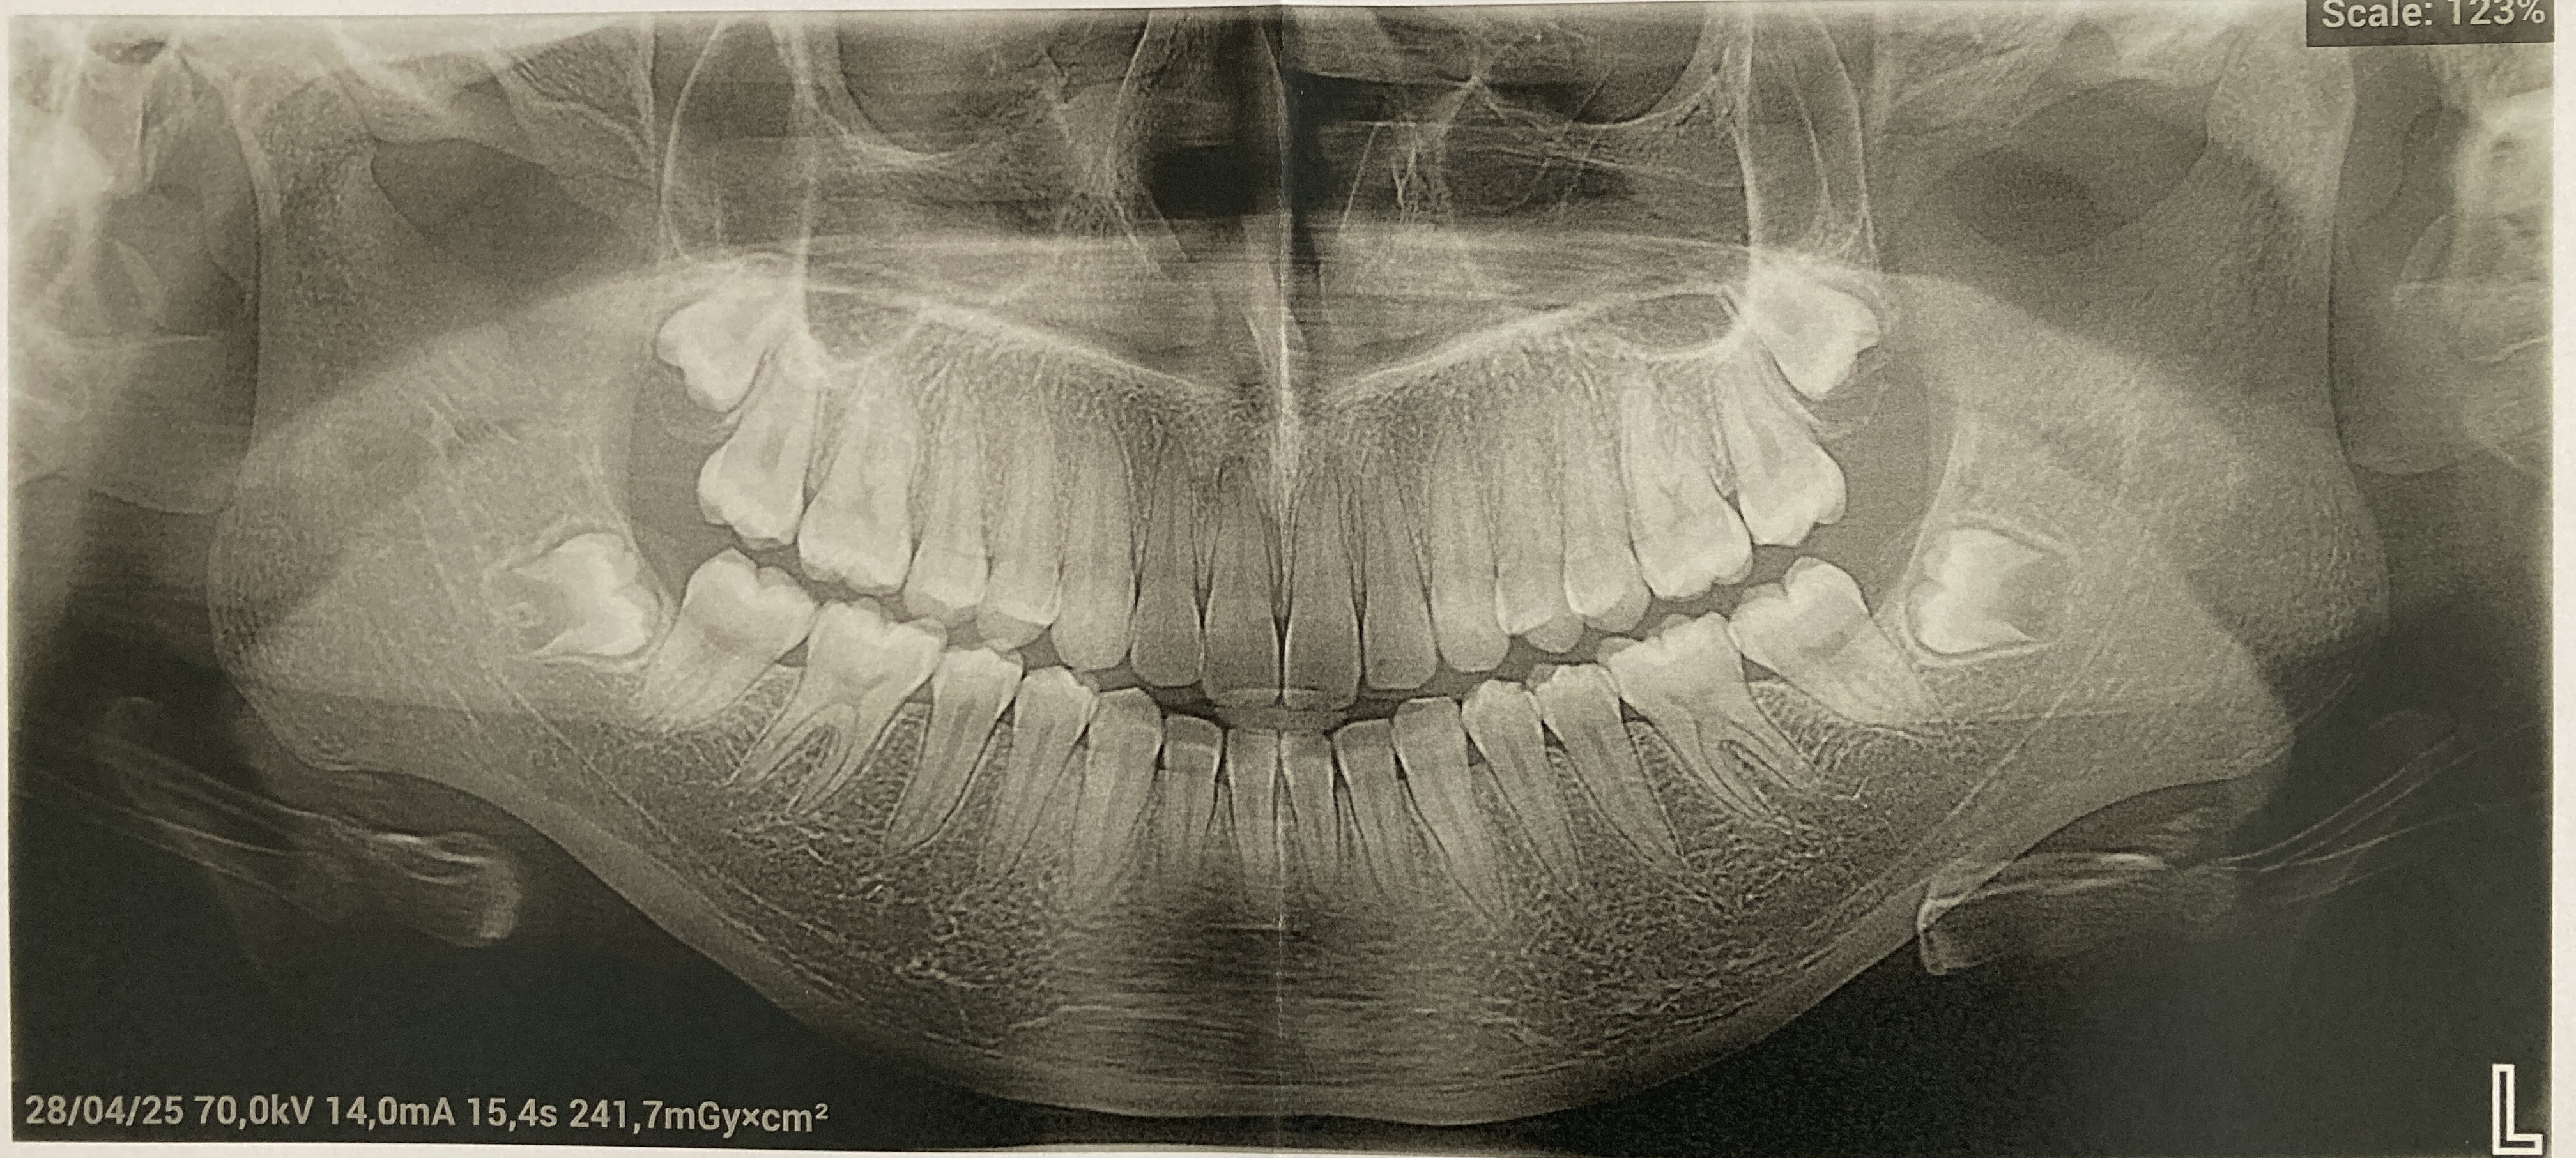

Mijn dochter (bijna 16) en ik waren van de week bij onze tandarts voor een jaarlijkse controle. We wonen in Luxemburg. De tandarts heeft een uitgebreide röntgenfoto gemaakt van mijn dochters gebit om de stand van de verstandskiezen te controleren. Zij adviseert nu om binnen een half jaar alle vier de verstandskiezen te verwijderen, voordat de wortels helemaal gevormd zijn. Ze geeft aan dat de kans groot is (90%) dat de kiezen niet optimaal zullen kunnen doorbreken en daarmee tot problemen zullen leiden. Ik voeg hierbij de röntgenfoto toe en hoop dat een deskundige hier op het forum ons kan adviseren. Alvast hartelijk dank!

Heel goed advies in mijn ogen. Ik zou niet wachten. Gevaar is dat als de wortels zich af vormen, ze dan heel dicht bij de zenuw buis komen. (zie buis op foto). Gevaar dan is dat bij verwijdering de zenuw geraakt kan worden met mogelijk beschadiging en uitval. Dus ik zou niet wachten ,,,,de wortels groeien.

Het gaat mij meer om de onder verstandkiezen vanwege de zenuwbaan. Boven hoeft geen problemen te geven. Denk niet dat preventief AB kuur nodig is. Ik stuur dit door naar de kaakchirurg maar dat is omdatik chirurgisch niet zo bedreven ben.